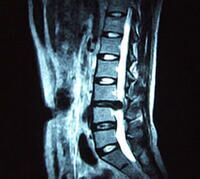

坐骨神经痛大多都是继发性的,为局部病变或其他组织压迫而引起的。但是很多人对坐骨神经痛的症状却知之甚少,很难做到及时的发现和治疗。经常在电脑前上班的你,是否时常感觉到腰部有疼痛的现象。如果有类似症状的话,您就需要到医院进行专业的检查,看看是不是患上了坐骨神经痛。下面我们就来详细的了解下坐骨神经痛的症状,做到早发现早治疗。

1、疼痛:患者腰部受到刺激时,会沿着坐骨神经痛的走行和分布出现放射性疼痛。放射性疼痛呈过电样的串麻感,由腰开始,放射至臀部和足部。患者小腿的外侧和大腿的后侧,会出现如针刺、刀割似的持续疼痛。患者在弯腰或活动时疼痛加重,休息后或侧卧的时候疼痛会有所减轻。

4、直腿抬高试验阳性:坐骨神经痛患者在进行直腿抬高试验时,因为疼痛出现上抬受限,而很难达到70°,是坐骨神经痛的典型症状。